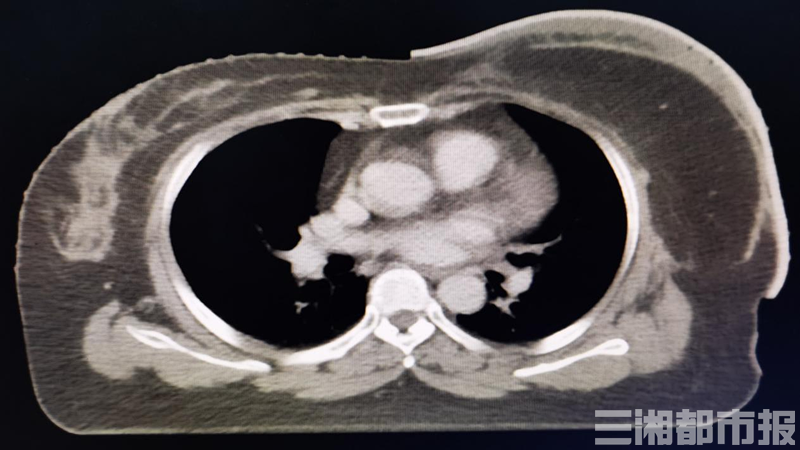

Take breast cancer as an example. When a patient develops a tumor, he may face resection of the body part. Ms. Yan, 51, is one such patient.Because she was diagnosed with left breast breast cancer, she underwent reconstruction such as modified radical mastectomy at Hunan Cancer Hospital in August this year.

. According to Ms. Yan’s condition, she has a high risk of recurrence and requires postoperative adjuvant radiotherapy.

However, 80-90% of tumor recurrence after radical mastectomy occurs in the subcutaneous lymphatics. Therefore, the affected chest wall is the main target area of radiotherapy after breast reconstruction for breast cancer. Both high-energy X-rays and electronic rays have dose-building effects, which will lead to Insufficient dose to the skin surface of the chest wall. The radiotherapy tissue compensator can effectively increase the radiation dose on the skin surface. However, due to the presence of the curvature of the chest wall after breast reconstruction and the uneven surface of the chest wall, there must be an air gap between the chest wall and the compensation membrane, which leads to the actual exposure dose of superficial tissues With greater uncertainty, the dose distribution in the target area does not match the radiotherapy plan, which affects the efficacy of radiotherapy.

According to Ms. Yan’s condition, Chief Physician Hu Ying, deputy director of the Second Department of Thoracic Radiotherapy of the hospital, and his team formulated a “personal exclusive” radiotherapy plan for Aunt Yan: innovatively3D printingTechnology combined with radiotherapy technology, successfully implemented3D printing

Grade, density is 1.06, close to water, can be reused and boiled for disinfection. It not only effectively improves the stability of the dose and dose of chest wall skin radiotherapy, but also provides precise and individualized treatment for patients.

Chief physician Hu Ying said,3D printingThe application of tissue compensator in breast reconstruction of breast cancer is currently a leading technology at home and abroad.3D printingTissue compensation is application3D printingTechnology, based on the data of each patient’s body surface curvature, uses a tissue compensator made of a simulated human tissue material with uniform texture, electron density close to water, short production time, and easy shaping.